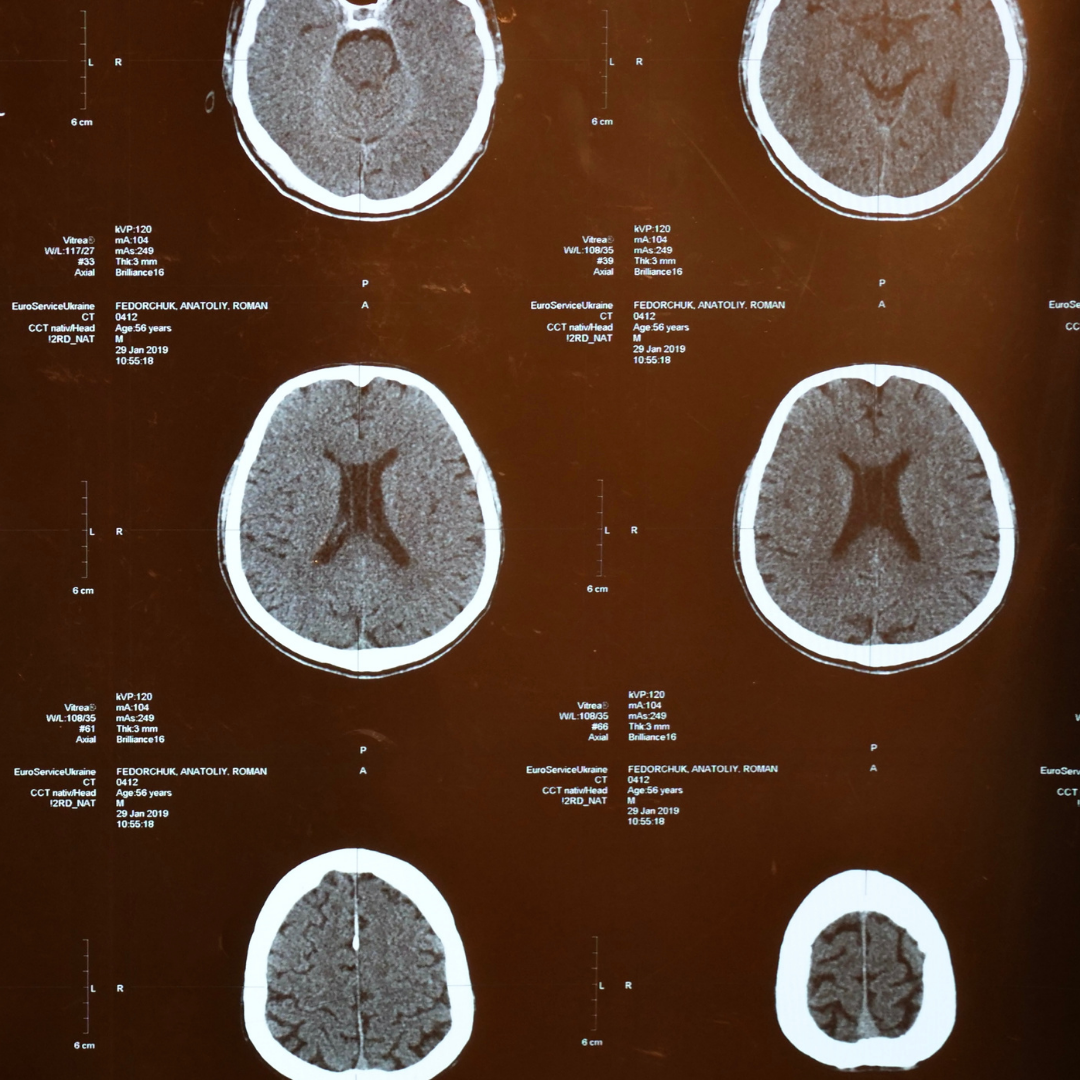

Stressors on the brain come in different shapes and sizes. Dr. Bredesen has identified over 30 possible stressors that could lead to cognitive decline.

They include:

glycotoxicity - persistantly elevated glucose levels in the blood, which causes glucose molecules to stick to proteins and lipids impairing their funtions.

chronic inflammation - our bodies natural defence against pathogens. erronously being turned on over a very long period of time.

Poor oxygenation - commonly occurs during sleep even in those who do not have obstructive sleep apnoea and those who do not snore.

vascular dysfuction - not getting enough oxygen to the brain

toxin exposure or an inability to clear toxins.

atrophy - a lack of hormonal support for the brain to maintain normal function.